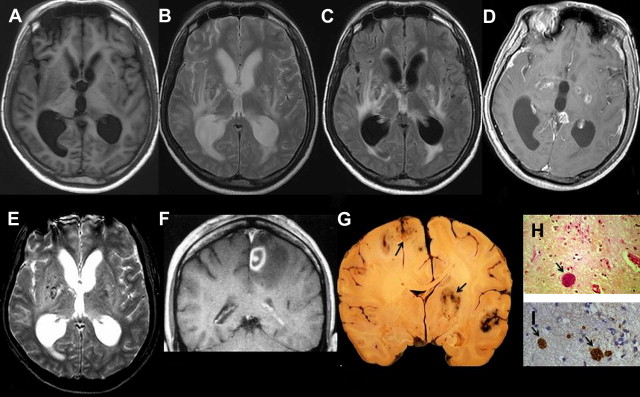

cerebral toxoplasmosis; these brain cysts may or may not ache, and come in a wide variety of sizes & shapes;